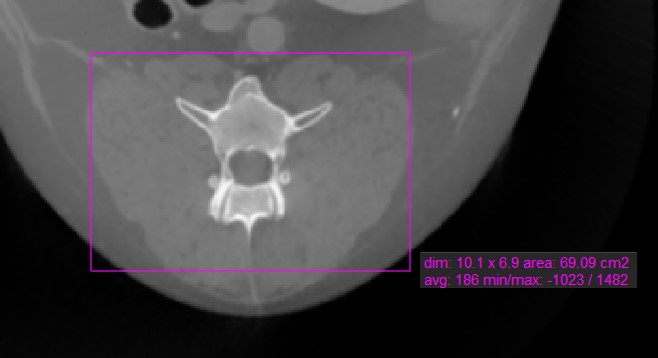

Rectangle¶

Select the Rectangle tool and assign it to one of the available mouse buttons. Start the measurement by pressing on the active image slice and drag the mouse to obtain a rectangular shape. Release the mouse

when satisfied with the size of the marked area.

All available measurement values are displayed alongside the measurement.

Modify the marked area by moving one of the four points of the rectangular shape using the Default tool.